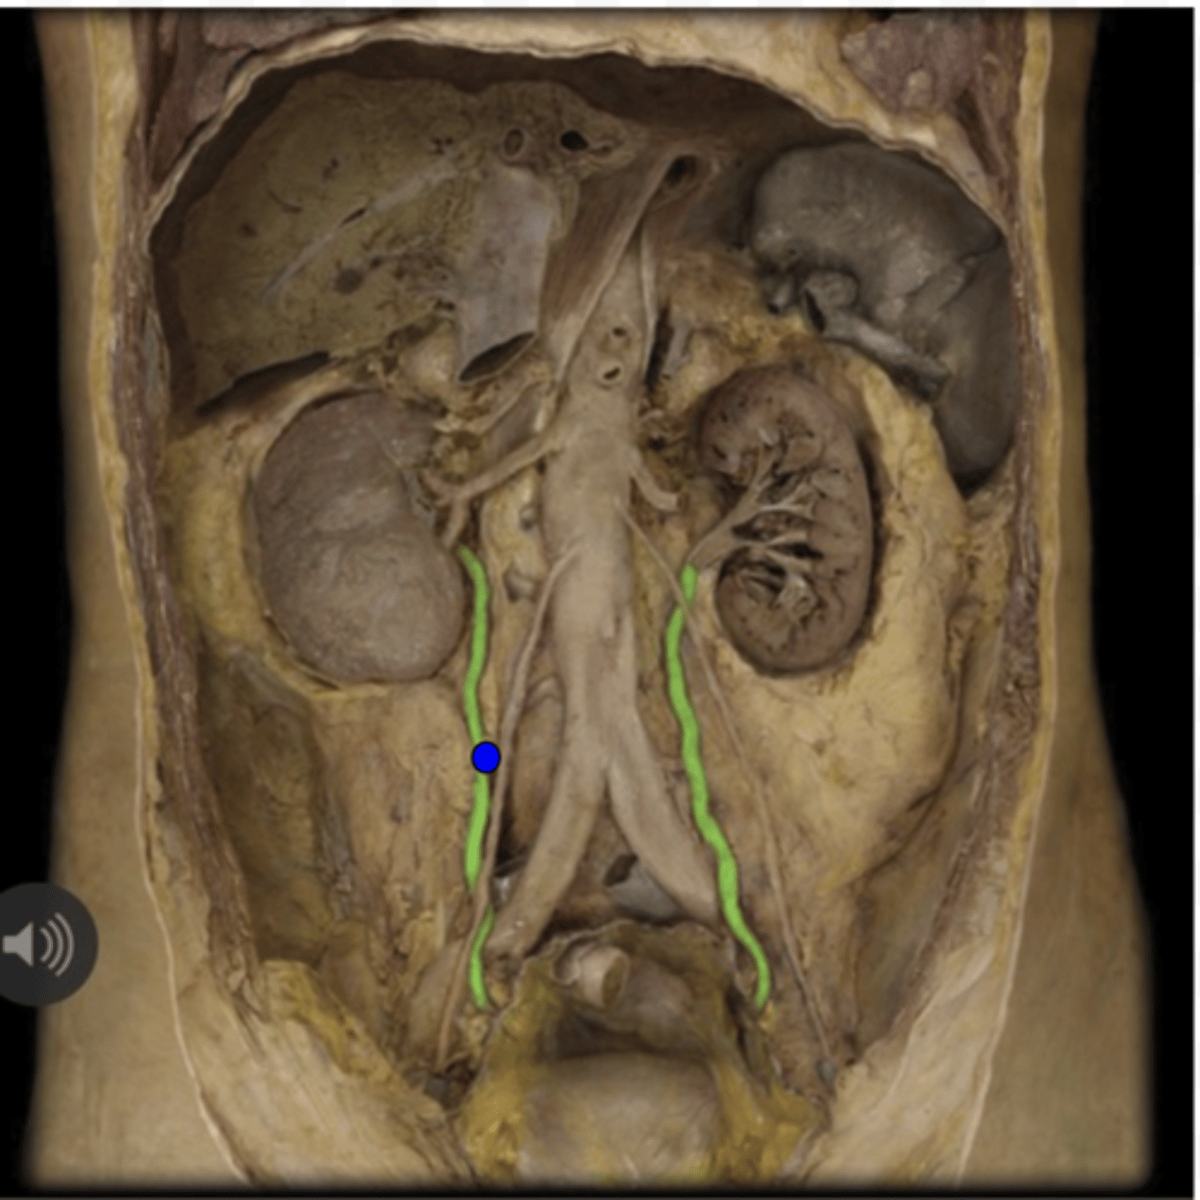

Right Ureter

Left Ureter